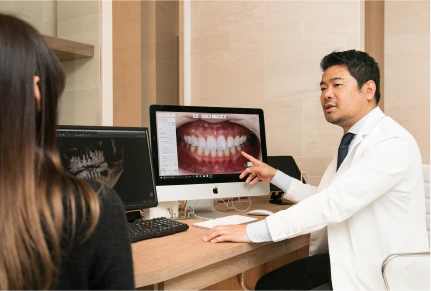

Careful Examination and Polite Counseling

All patients will undergo some examinations such as cavity check, periodontal pocket depth, x-ray, and dental photo at first appointment. Then, Dr. Maruo will explain present situation, problem, solution, treatment period, and estimation. So, it will take around 60 minutes at first appointment.